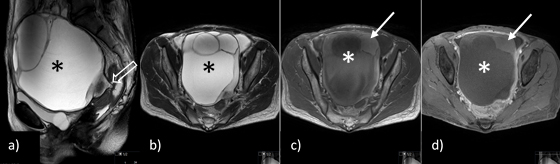

Pelvic MRI showed a large multicystic pelvic tumour arising from the left adnexa, with T1WI hyperintense content that did not enhance in post-contrast sequences, in keeping with subacute intra-tumoural haemorrhage and/or necrosis (Fig. 3).

Although there were no categorical signs of ovarian torsion such as the whirlpool sign, the clinical context indicating systemic inflammation/infection (leucocytosis with reactive thrombocytosis) and the ipsilateral uterus deviation (which would not be expected by the mass effect of a large tumour), the hypothesis of an ovarian tumour with torsion and ovarian necrosis with possible super-infection was raised, and the patient underwent emergent surgical intervention.

Figure 3: Pelvic MRI: a) sagittal and b) axial T2-weighted imaging (WI), c) axial T1WI and d) fat suppressed T1WI after the administration of contrast, show a large multicystic pelvic tumour (*) arising from the left adnexa, with a beak-like projection to the adnexal region that could suggest a torsed ending (open arrow), although twisting of the ovarian pedicle was not identified, with T1WI hyperintense content that does not enhance in post-contrast sequences in keeping with subacute intra-tumoural haemorrhage and/or necrosis.